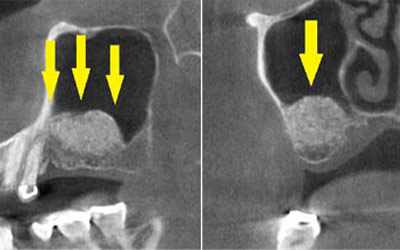

患者様のインプラント治療前のレントゲン写真です。右下顎大臼歯2本の抜歯後のレントゲン写真で、写真の黄色矢印は、歯の周囲の歯槽骨が大きく吸収されてしまっていました。

写真のように、CTで見ると、骨吸収の様子が良く分かり、下顎骨の中を通る神経近くまで骨がありませんでした。

さらに、CTで、別な方向から見ると、黄色矢印のように骨が吸収されていて、緑色矢印で示される神経の通る管に迫り、インプラントが埋入できるような骨量はありませんでした。

インプラントを埋入するために、骨を増やす方法はいくつかありましたが、この場合、患者様ご自身の骨をブロック状で移植するのが最も適していると判断し、自家骨移植術を行ないました。患者様ご自身の下顎前歯の下方から骨を採取して、骨がなかった部位に移植し、スクリューで固定したCT画像です。黄色矢印部分が、2つの骨片を移植して、固定したところです。

手術後の、別な方向からみたCT画像です。術前に大きく吸収されていた部分に、骨のブロックが移植され、骨が造成されています。真っ白にピンのように写るのは、骨を固定した小さなスクリューです。